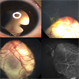

- RD, chorioretinal coloboma

- Color fundus photograph of a 43 year old male post retinal detachment surgery in a case of iridofundal coloboma.